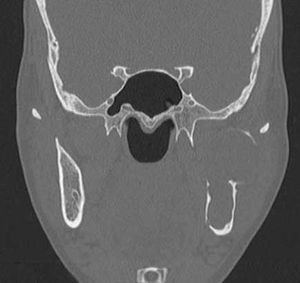

Gorlin-Goltz SyndromeByVenkatraman Indiran, MDDecember 4th 2013Case History: A 32-year-old patient presented for CT scan of the face with history of a painless swelling over the left cheek for four months.